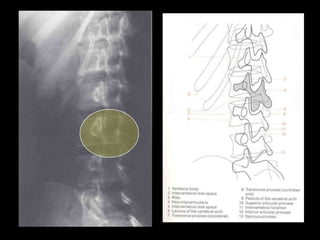

This document provides an overview of normal musculoskeletal imaging. It discusses basic x-ray concepts and densities. It then reviews normal anatomy as seen on x-rays of the skull, spine, pelvis, chest, and extremities. Key anatomical structures are labeled on example x-rays for the shoulder, hip, knee, and foot. Quizzes are included to test recognition of anatomical structures and patient age based on x-rays.